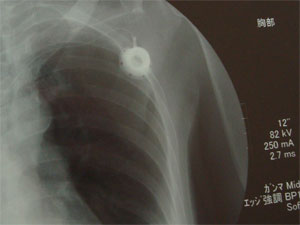

こちら、また胸の中のひまわりです。

6月15日13時半より、CVポート埋め込み術を行いました。13時まで仕事をして時間年休をいただき、患者側が駆け込みという状況でした。

さて、埋め込みの方は、エコーで刺針位置を確認すると、まだ脱水がひどい状態ではないので予定通りできました。